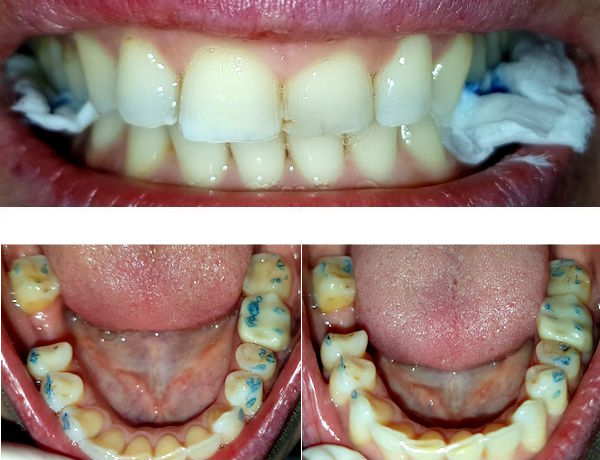

24-jähriger Patient (17.11.2025 / 8888)

Anamnese: Der Patient musste wegen einer kieferorthopädischen Behandlung 4+4 ziehen und 765+567 nach vorne verschieben lassen. Deshalb ist eine Minderbelastung des Kauzentrums 6-6 entstanden. Um besser kauen zu können, hat er nur noch links gebissen. Dabei ist aber +7 elongiert und ein Vorkontakt auf +-7 entstanden, der ihn störte. Er hat deshalb schon fünf verschiedene Knirscherschienen erhalten.

Therapie: Die mesialen Höcker des Zahnes 6- konnten ganz einfach mit Komposit erhöht werden.

Das Kaugefühl war dann sofort besser.

In der nächsten Sitzung wird auch noch der Zahn 5- erhöht, um das Kauzentrum noch etwas mehr zu vergrössern.

Vorbehalt: das Kaugefühl ist gut geblieben.

Der Patient hatte nach der kieferorthopädischen Behandlung kein gutes Bissgefühl. Die Anfärbung zeigt, dass die wichtigsten Molaren 6-6 fast nicht belastet werden.

Mit Komposit wurde auf die Molaren 76-6 je ein Witzgall-Höcker aufgesetzt. Diese befinden sich nicht am gewöhnlichen Ort, sondern dort, wo sie den Biss am besten unterstützen. Bei der kieferorthopädischen Behandlung mussten die oberen Molaren etwas nach vorne verschoben werden und passten deshalb nicht mehr gut zu den unteren.